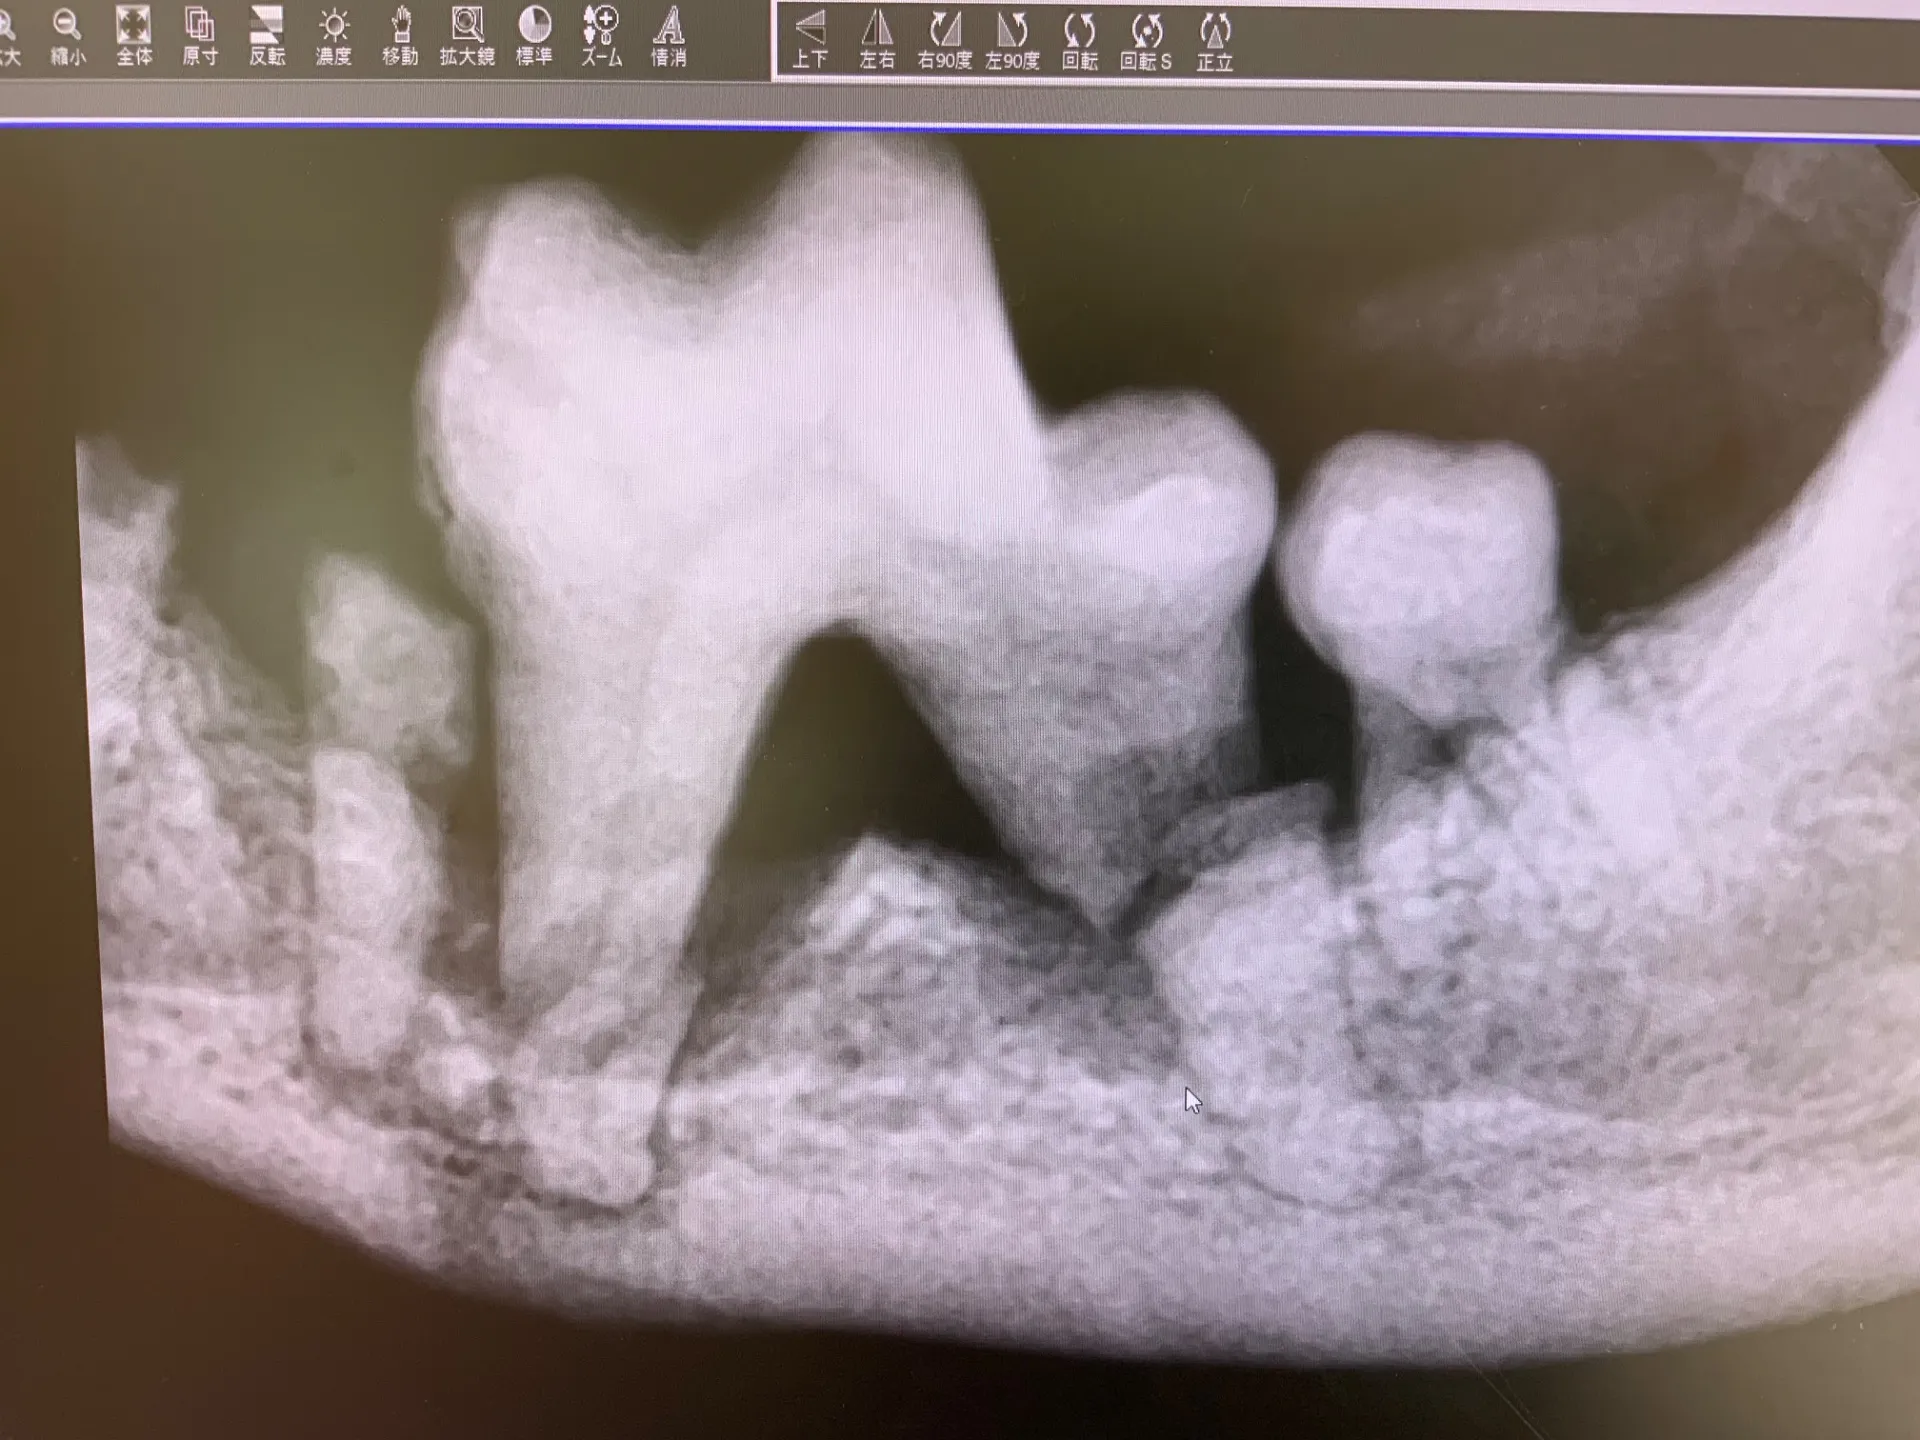

DENTALペットの口腔内の健康を守るための総合的なデンタルケアについてご紹介いたします。ペットの健康は口腔内から始まると言われるほど、歯と歯肉の健康は大切です。当院では、歯科レントゲンや歯科専…

一歩踏み込んだ、高度な歯科治療。大切な歯を残すための選択肢がここにあります対応症例のご紹介(写真付き解説)(小型犬に多く発生をみる)「乳歯遺残」などは、将来の歯列不正や歯周病の原因になります。…